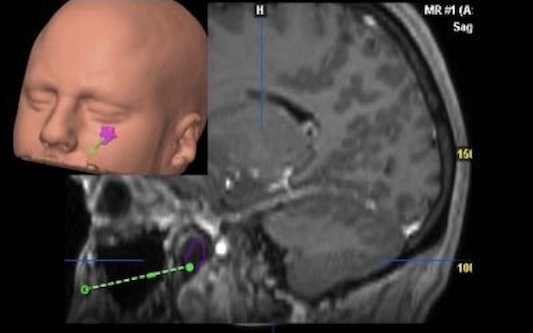

En la mayoría de los casos el tratamiento consistirá en la extirpación del tumor. En MAXILOFACE aplicamos técnicas quirúrgicas poco invasivas que permiten una rápida recuperación del paciente y un buen resultado estético. El Dr. Néstor Montesdeoca es pionero en España en la utilización del neuronavegador para la localización del tumor de órbita y su extirpación sin comprometer estructuras vitales para la visión.

Empleamos de forma rutinaria planificación 3D y prótesis a medida para la reconstrucción de la órbita.